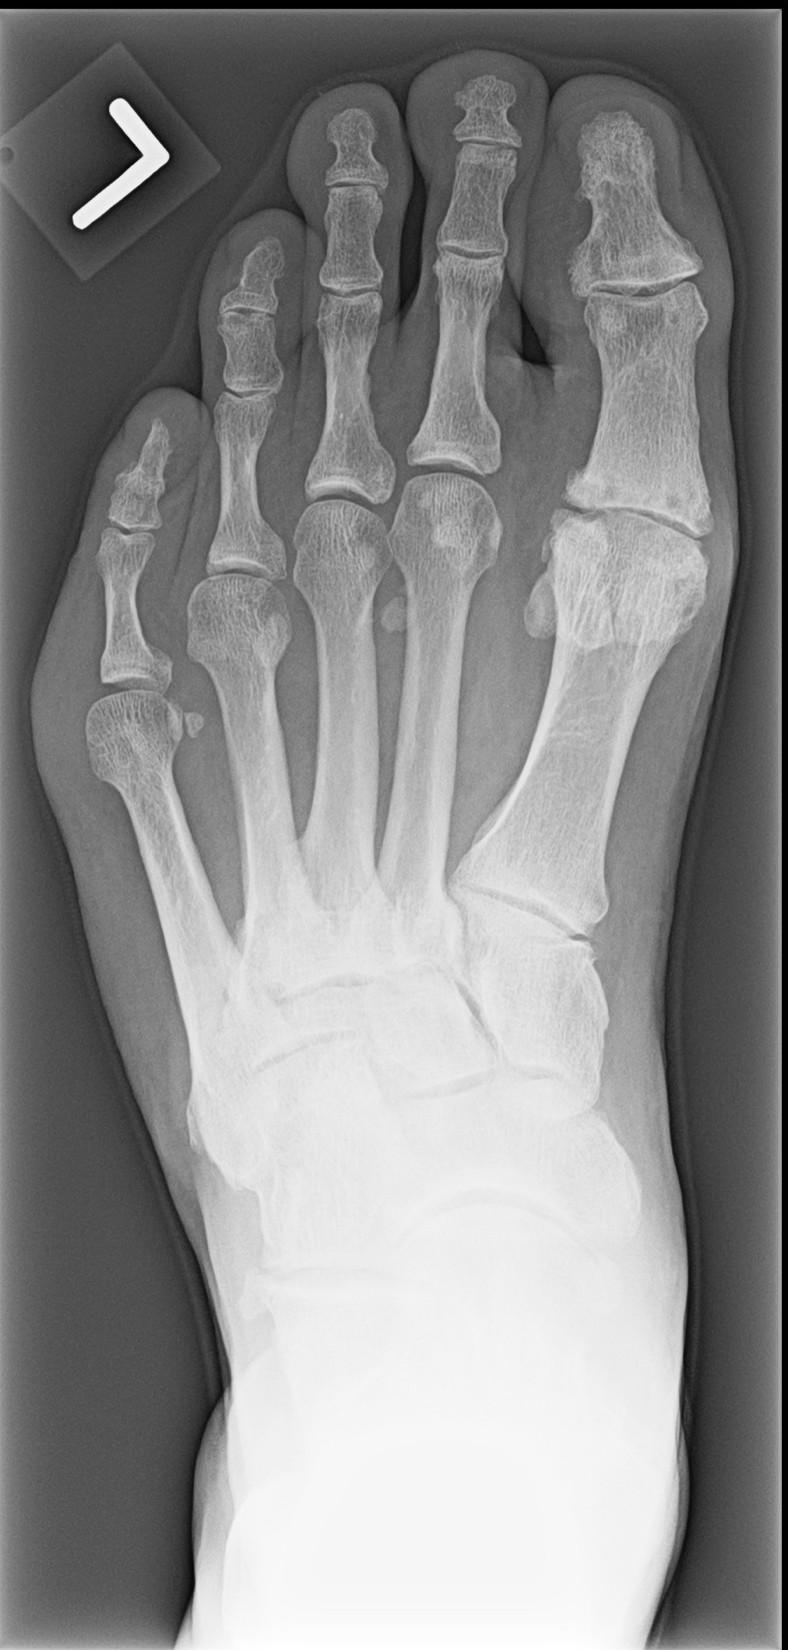

Living with midfoot OA can be a daily struggle marked by persistent pain, stiffness or swelling. This can significantly affect mobility, making simple activities such as walking, prolonged standing, or climbing stairs difficult or exhausting.1,7,8 Discomfort often worsens during and after activity but can also occur at rest. Pain is just one aspect experienced by people living with midfoot OA. Changes in foot posture, such as flattening of the arch (Figure 2) and bony deformities, are common and can make finding suitable footwear difficult.9